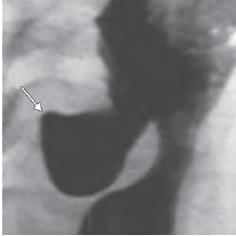

A 70-year-old patient presented with history of fever, halitosis, night cough and regurgitation of food in the mouth. On examination there is a pulsatile swelling on left side of neck which produces gurgling sound on compression. What is the most likely diagnosis, by looking at the given barium swallow study of the patient? (NEET-PG 2020)

Detailed Solution for Test: Anatomy - 3 - Question 21

Zenker’s diverticulum is a false diverticulum located in the pharyngoesophageal region. This condition arises due to esophageal dysmotility, which leads to the herniation of mucosal tissue at the Killian triangle, situated between the thyropharyngeal and cricopharyngeal segments of the inferior pharyngeal constrictor. The symptoms typically presented include:

• dysphagia

• obstruction

• gurgling sounds

• aspiration

• foul breath (halitosis)

• neck mass

It is most frequently observed in elderly males.